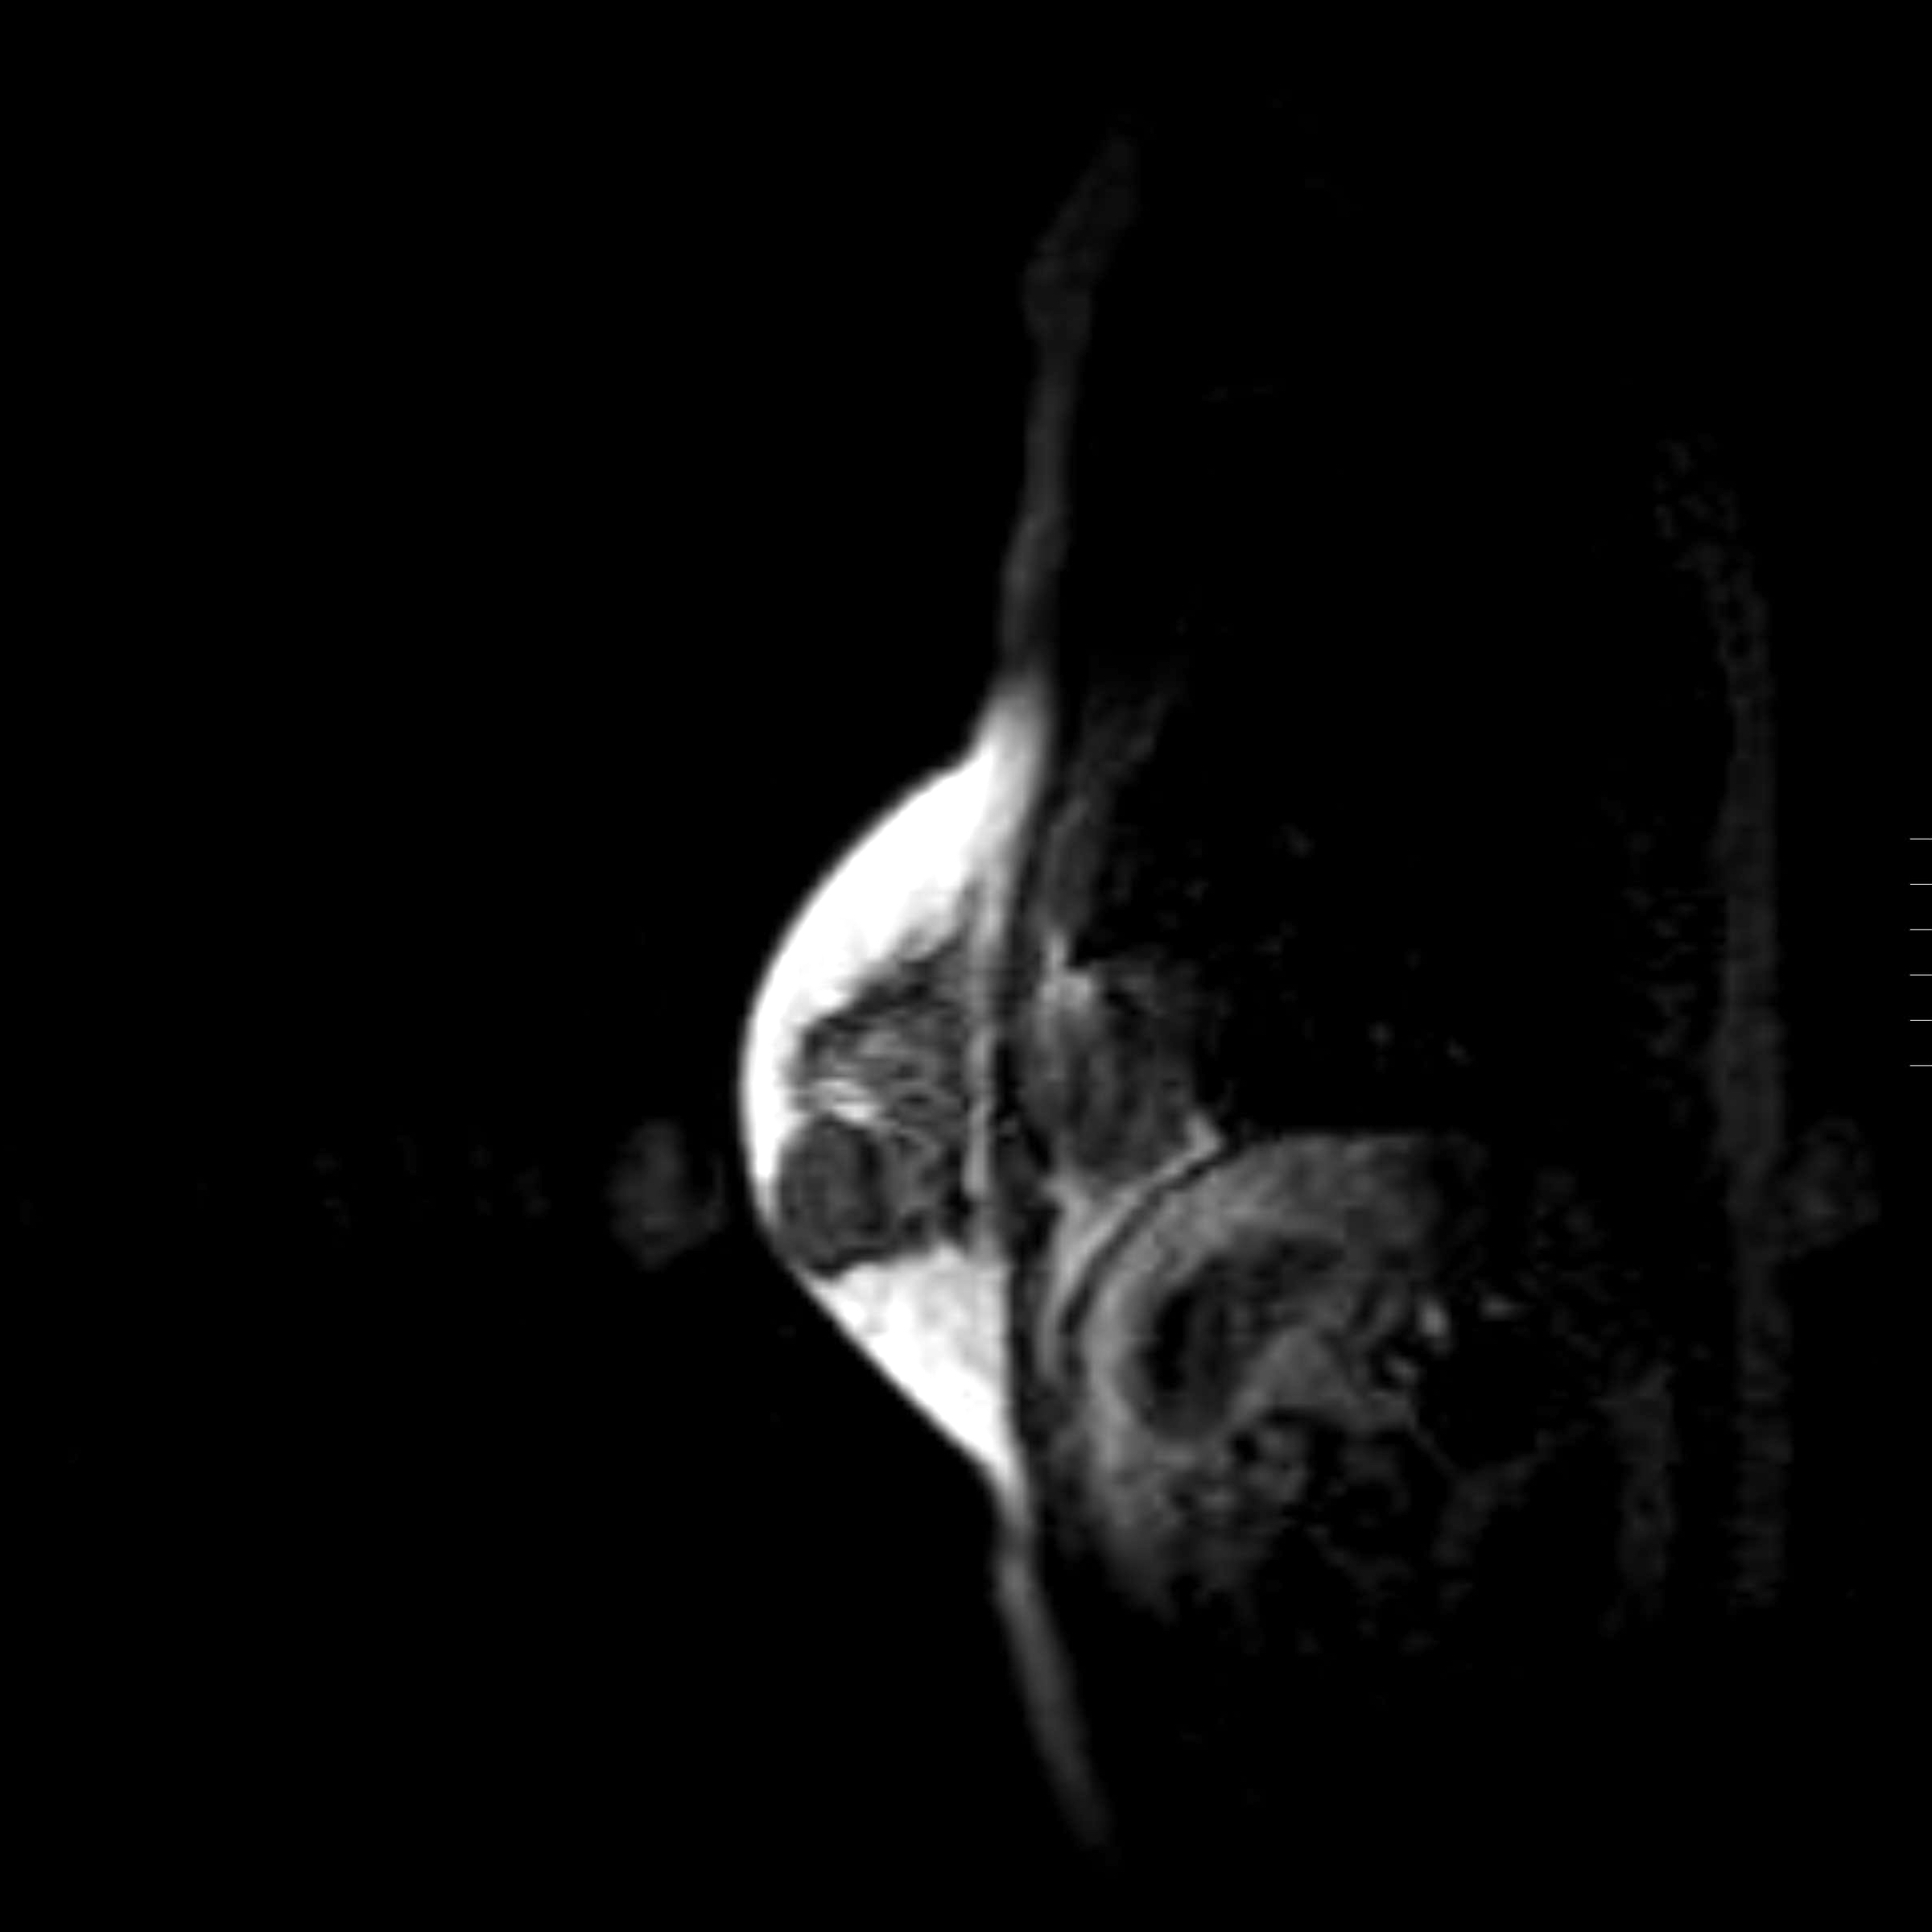

Radiology description

- Conventional imaging modalities for assessment of radiological response includes mammography, ultrasound, MRI

- Radiological response is defined by resolution of original imaging finding (complete response) or by change in lesion size

- Radiological response is predictive of outcome and correlates with pathological response (Eur J Surg Oncol 2021;47:232)

- MRI is more sensitive and is preferred over other imaging modalities (Anticancer Res 2014;34:1219, Insights Imaging 2013;4:163)

- Functional imaging is also used for assessment of radiological response

- Response is defined by normalization of tracer uptake (complete response) or by change in tracer uptake (Radiology 2017;285:358)

- MRI is more accurate in predicting complete pathological response than PET / CT (Oncologist 2016;21:931)

Radiology images